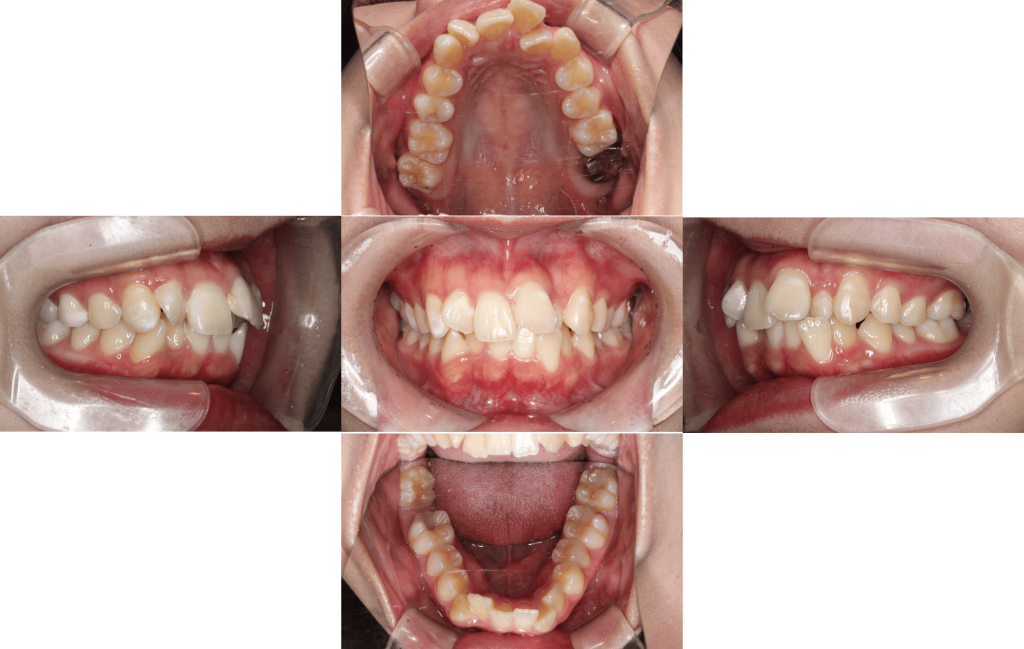

Before

初診